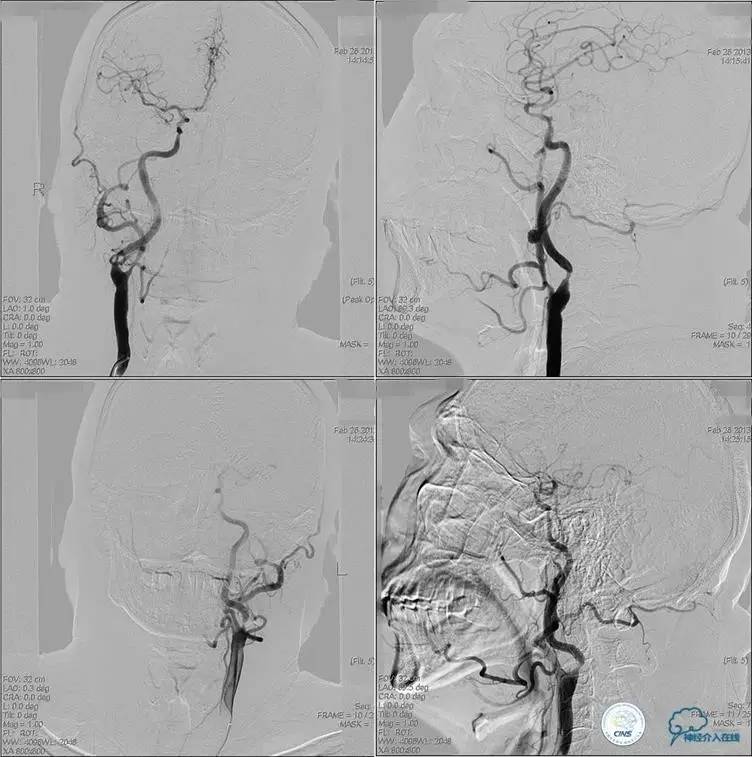

▼术前DSA

▼术中DSA

▼术后DSA